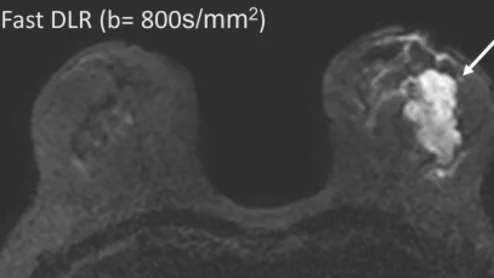

Deep learning reconstruction improves breast MRI quality

The use of DLR also provides greater flexibility with protocols in comparison to conventional single-shot echo-planar imaging.